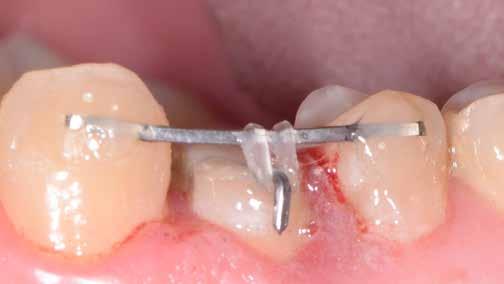

A szakirodalomban fellelhető eredmények alapján kerámia héjak ragasztására a kontaminációtól mentes, frissen vágott zománc felszín a legalkalmasabb. A hosszú távú sikeresség elérésének további feltétele a fogak konzervatív módon történő preparálása, továbbá a ragasztás kofferdám felhelyezésével biztosított, abszolút izolálásban történő kivitelezése. Úgy véljük, hogy a fenti faktorok biztosították a cikkben bemutatásra kerülő esetek – 5 évvel az átadás után megfigyelhető – sikerességét. A kofferdám izolálás alkalmazása számos előnyt biztosít a gyakorló fogorvos számára. Megakadályozza a munkaterület nyállal, vérrel, vagy szulkusz-váladékkal történő kontaminációját, és javítja a kezelendő területre való rálátásunkat. A fogak kerámia héjak ragasztása előtt történő izolálása azonban gyakran kihívást jelenthet a kevesebb klinikai tapasztalattal rendelkező fogorvosok számára. Jelen esetbemutatásban ismertetjük a kofferdám felhelyezésének lépéseit és néhány olyan gyakorlati tanácsot, amelyek jelentősen megkönnyíthetik a munkánkat, azokban az esetekben, amikor a második kisőrlőfogak közti területet kívánjuk kofferdám segítségével izolálni. A kofferdám kapcsok segítségével került rögzítésre, majd fogakat körülvevő széleit óvatosan az ínybarázdába forgattuk. A kerámia héjak számára előkészített fogakra ragasztás előtt egyenként kapcsokat helyeztünk annak érdekében, hogy a kerámia héjak rögzítése ideális körülmények között történhessen. A lépések részletes ismertetése segítséget jelenthet – a kevesebb klinikai tapasztalattal rendelkező fogorvosok számára – az abszolút izolálás megvalósításához szükséges lágyrészmenedzsment megértéséhez. Ezek az ismeretek rendkívül hasznosak lehetnek, ha a jövőben a kerámia héjak ragasztását megfelelő módon megvalósított kofferdám izolálás mellett kívánják kivitelezni. A cikkben ismertetett módszerek alkalmazásával az abszolút izolálás megvalósítható, a gumilepedő – vérzés nélkül – ínybarázdába történő beforgatására, és a ragasztáshoz szükséges idő csökkentésére.

A kofferdám izolálás felhelyezése egy nagyon jól meghatározott lépésekből álló folyamat. A fogorvosnak tisztában kell lenni azzal, hogy lehet a lágyrészeket finoman manipulálni az applikálás során, mivel csak így érhető el a tökéletesen izolált munkaterület. A kapcsok nem megfelelő módon történő felhelyezése ínyvérzés kialakulásához vezet, amely a ragasztás szempontjából rendkívül kedvezőtlen helyzetet teremthet.

Az előzetes állapotfelmérést és a kezelés megtervezését követően a fogakat minimál invazív módon preparáltuk (1. a-b ábrák), majd az előkészített fogak ínybarázdáiba fonalbehelyező eszköz segítségével (113 Serrated Gingival Cord Packer, Hu-Friedy, Chicago, Illinois) teflonszalagot helyeztünk (Loctite Thread Seal Tape, Henkel Loctite Corp., Egyesült Államok), (1. c ábra). A hagyományos retrakciós fonalak helyett, a rugalmasságuk miatt előnyösebbnek tartjuk a teflonszalagok használatát. A kofferdámot (Dental Dam, Nic Tone, Bukarest, Románia) az előkészített fogakon kívül, az azoktól disztálisan elhelyezkedő egy-egy fognak megfelelően is perforáltuk.

Mivel a felső fogív első kisőrlőfogtól ellenoldali első kisőrlőfogig terjedő részét terveztük kerámia héjak segítségével ellátni (14-24), ezért az izolálást ugyanezen fogív második kisőrlőfogtól második kisőrlőfogig terjedő részére (15-25) helyeztük fel (2. a ábra). A kofferdám rögzítését a második kisőrlőfogakra helyezett kapcsok segítségével (Rubber Dam Clamps #2, Hu-Friedy, Chicago, Illinois, Egyesült Államok) biztosítottuk (2. b ábra). Ezt követően a gumilepedő fogakat körülvevő szélét kézi fonalbehelyező eszközzel és finom levegőáramlattal az ínybarázdákba forgattuk. A folyamat a következőképpen zajlott: a kézi eszközzel a kofferdámot a fognyaknak megfelelően finoman a szulkusz irányába fordítjuk, majd az eszköz végét a fognyaknak megfelelően vezetjük, miközben a lepedőt a puszterből jövő levegő segítsé-

gével finoman az ínybarázdába fordítjuk (2. c ábra). Azokra a fogakra, amelyekre aktuálisan héjakat akartunk helyezni, ezen felül kiegészítő kapcsokat is helyeztünk (Hygenic Brinker Clamp #B4, Coltene/Whaledent Inc., Cuyahoga Falls, Ohio, Egyesült Államok), (2. d ábra) Ebben a stádiumban érdemes a héjakat még bármilyen ragasztóanyag vagy próbapaszta nélkül a helyükre illeszteni (dry tryin). Erre azért volt szükség, hogy még a tényleges ragasztási folyamat megkezdése előtt ellenőrizni tudjuk a restaurátum és a fog pontos illeszkedését, valamint a széli záródási vonalhoz való akadálytalan hozzáférést (3. a ábra). Ideális esetben a héjak felhelyezését párosával, a középvonaltól disztál felé haladva végezzük. Ennek megfelelően a jobb (1.1) és bal felső nagymetszőfogakra (2.1) kapcsokat helyeztünk, majd a szomszédos fogakat teflonszalag segítségével izoláltuk. Ezt követően az 1.1-es és 2.1-es fogak héjak elhorgonyzására szolgáló felszíneit 32%os foszforsavval (Uni-Etch w/BAC, Bisco Dental, Schaumburg, Illinois, Egyesült Államok) 30 másodpercen keresztül kondicionáltuk. Ez után a felszínek vízzel történő lemosása és óvatosan

leszárítása következett (3. b ábra). A fogfelszínek előkészítésének utolsó lépéseként a primert és az adhezívet (OptiBond FL, Kerr Dental Orange, Kalifornia, Egyesült Államok) a gyártói javaslatnak megfelelően a felszínekre applikáltuk, majd 20 másodpercen keresztül polimerizációs lámpával világítottuk (Valo LED Curing Light, Ultradent Products Inc., South Jordan, Utah). Az 1.1-es és 2.1-es fogakat borító héjak ragasztása során világos színű, fényre kötő ragasztócementet (Variolink Esthetic LC, Ivoclar Vivadent, Schaan, Liechtenstein) alkalmaztunk. A ragasztóanyagot először a héjak belső felszínére vittük fel, majd ezeket az előkészített fogfelszínekre helyeztük (3. c ábra). Az approximális felszíneken megjelenő cementfelesleget egy ecset (Profi Natural Bristle Brush, Renfert, Hilzingen, Németország) és fogselyem (Oral-B Glide Pro-Health Deep Clean Floss, Procter & Gamble, Cincinnati, Ohio, Egyesült Államok) segítségével még a ragasztóanyag megvilágítása előtt eltávolítottuk. A megvilágítás során a különböző fogfelszíneket (labiális, meziális, disztális és incizális) 20-20 másodpercen keresztül világítottuk meg (3. d ábra)

egy kapocsfeszítő (4 Rubber Dam Clamp Forceps, Hu-Friedy, Chicago, Illinois, Egyesült Államok) segítségével eltávolítottuk (4. a-b ábrák). Ezután a kismetszőfogak előkészítése következett. Még a kapcsok felhelyezése előtt a szomszédos fogakat, azaz a jobb és bal felső szemfogat, valamint a felső nagymetszőfogakat (1.3, 1.1, 2.1, 2.3) teflonszalaggal izoláltuk (4.c. ábra). Ezután a korábban részletezett ragasztási protokollt követve a kismetszőfogakra készített héjakat beragasztottuk. Ezt a folyamatot a felső szemfogak, és végül az első kisőrlőfogak esetében is megismételtük (4. d-e. ábrák)

A fognyaki területen és a fogközökben megjelenő cementfelesleget egy speciális kézi kürett (LM-Arte Eccesso, Planmeca, Helsinki, Finnország), approximális polírszalag és egy #12-es szikepenge (Surgical Scalpel Blade No. 12., Salvin Dental Specialties, Charlotte, Észak-Karolina, Egyesült Államok) segítségével távolítottuk el (5. a–c. ábrák)